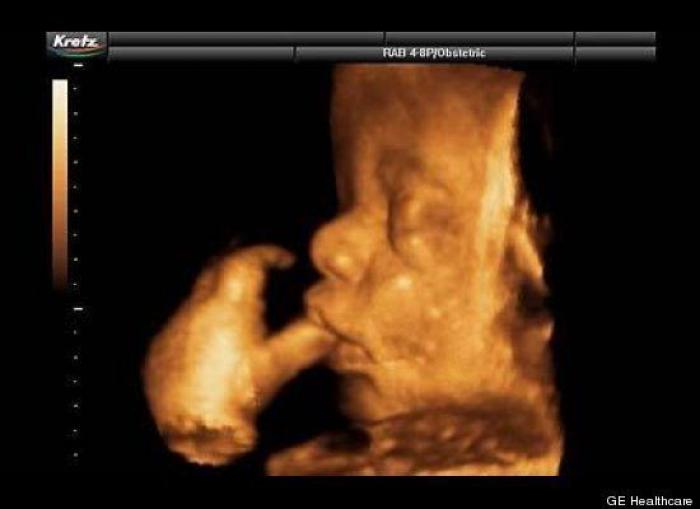

En esta galería puedes ver en fotos como es el desarrollo de un feto de semana en semana:

Desarrollo del feto, en fotos

Ver la galería